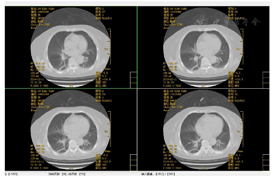

4.治疗中期及拔管前功能评估:未吸氧,血氧饱和度正常范围,生命体征平稳。主动张口幅度1.5 cm,被动张口幅度2.5 cm,自主咳嗽能力正常、自主清嗓较稍减弱,咽反射正常,吞咽启动减慢,喉上抬范围1.0 cm,简易吞咽诱发试验正常。气切管固定稳妥,未见异常分泌物。经气切口通气,呼吸平稳;膈肌移动度及呼吸肌肌力和耐力正常。Brunnstrom运动功能评定:左上肢3期、左手3期、左下肢4期。左侧肢体浅感觉较对侧减退,左肘及左膝关节平面以下感觉减弱。颈部被动活动无明显受限。站立平衡1级及坐位平衡2级。完善吞咽造影检查:可进食1、2、3号食物,吞咽造影提示患者吞咽启动减慢,吞咽耐力部分下降(视频2)。拔管前辅助检查评估:(1)完善颈部CT未见颈部无软组织肿胀及呼吸道受压;(2)电子鼻咽喉镜未见气道狭窄,声门开放可(视频3);(3)未吸氧情况下血气分析未见明显异常,肺功能大致正常;(4)肺部CT(图4、图5)提示感染基本控制,炎症明显吸收,血感染指标正常;(5)连续堵管训练24 h,患者血氧饱和度及血气分析正常。

5.拔除气管导管,成功堵管。